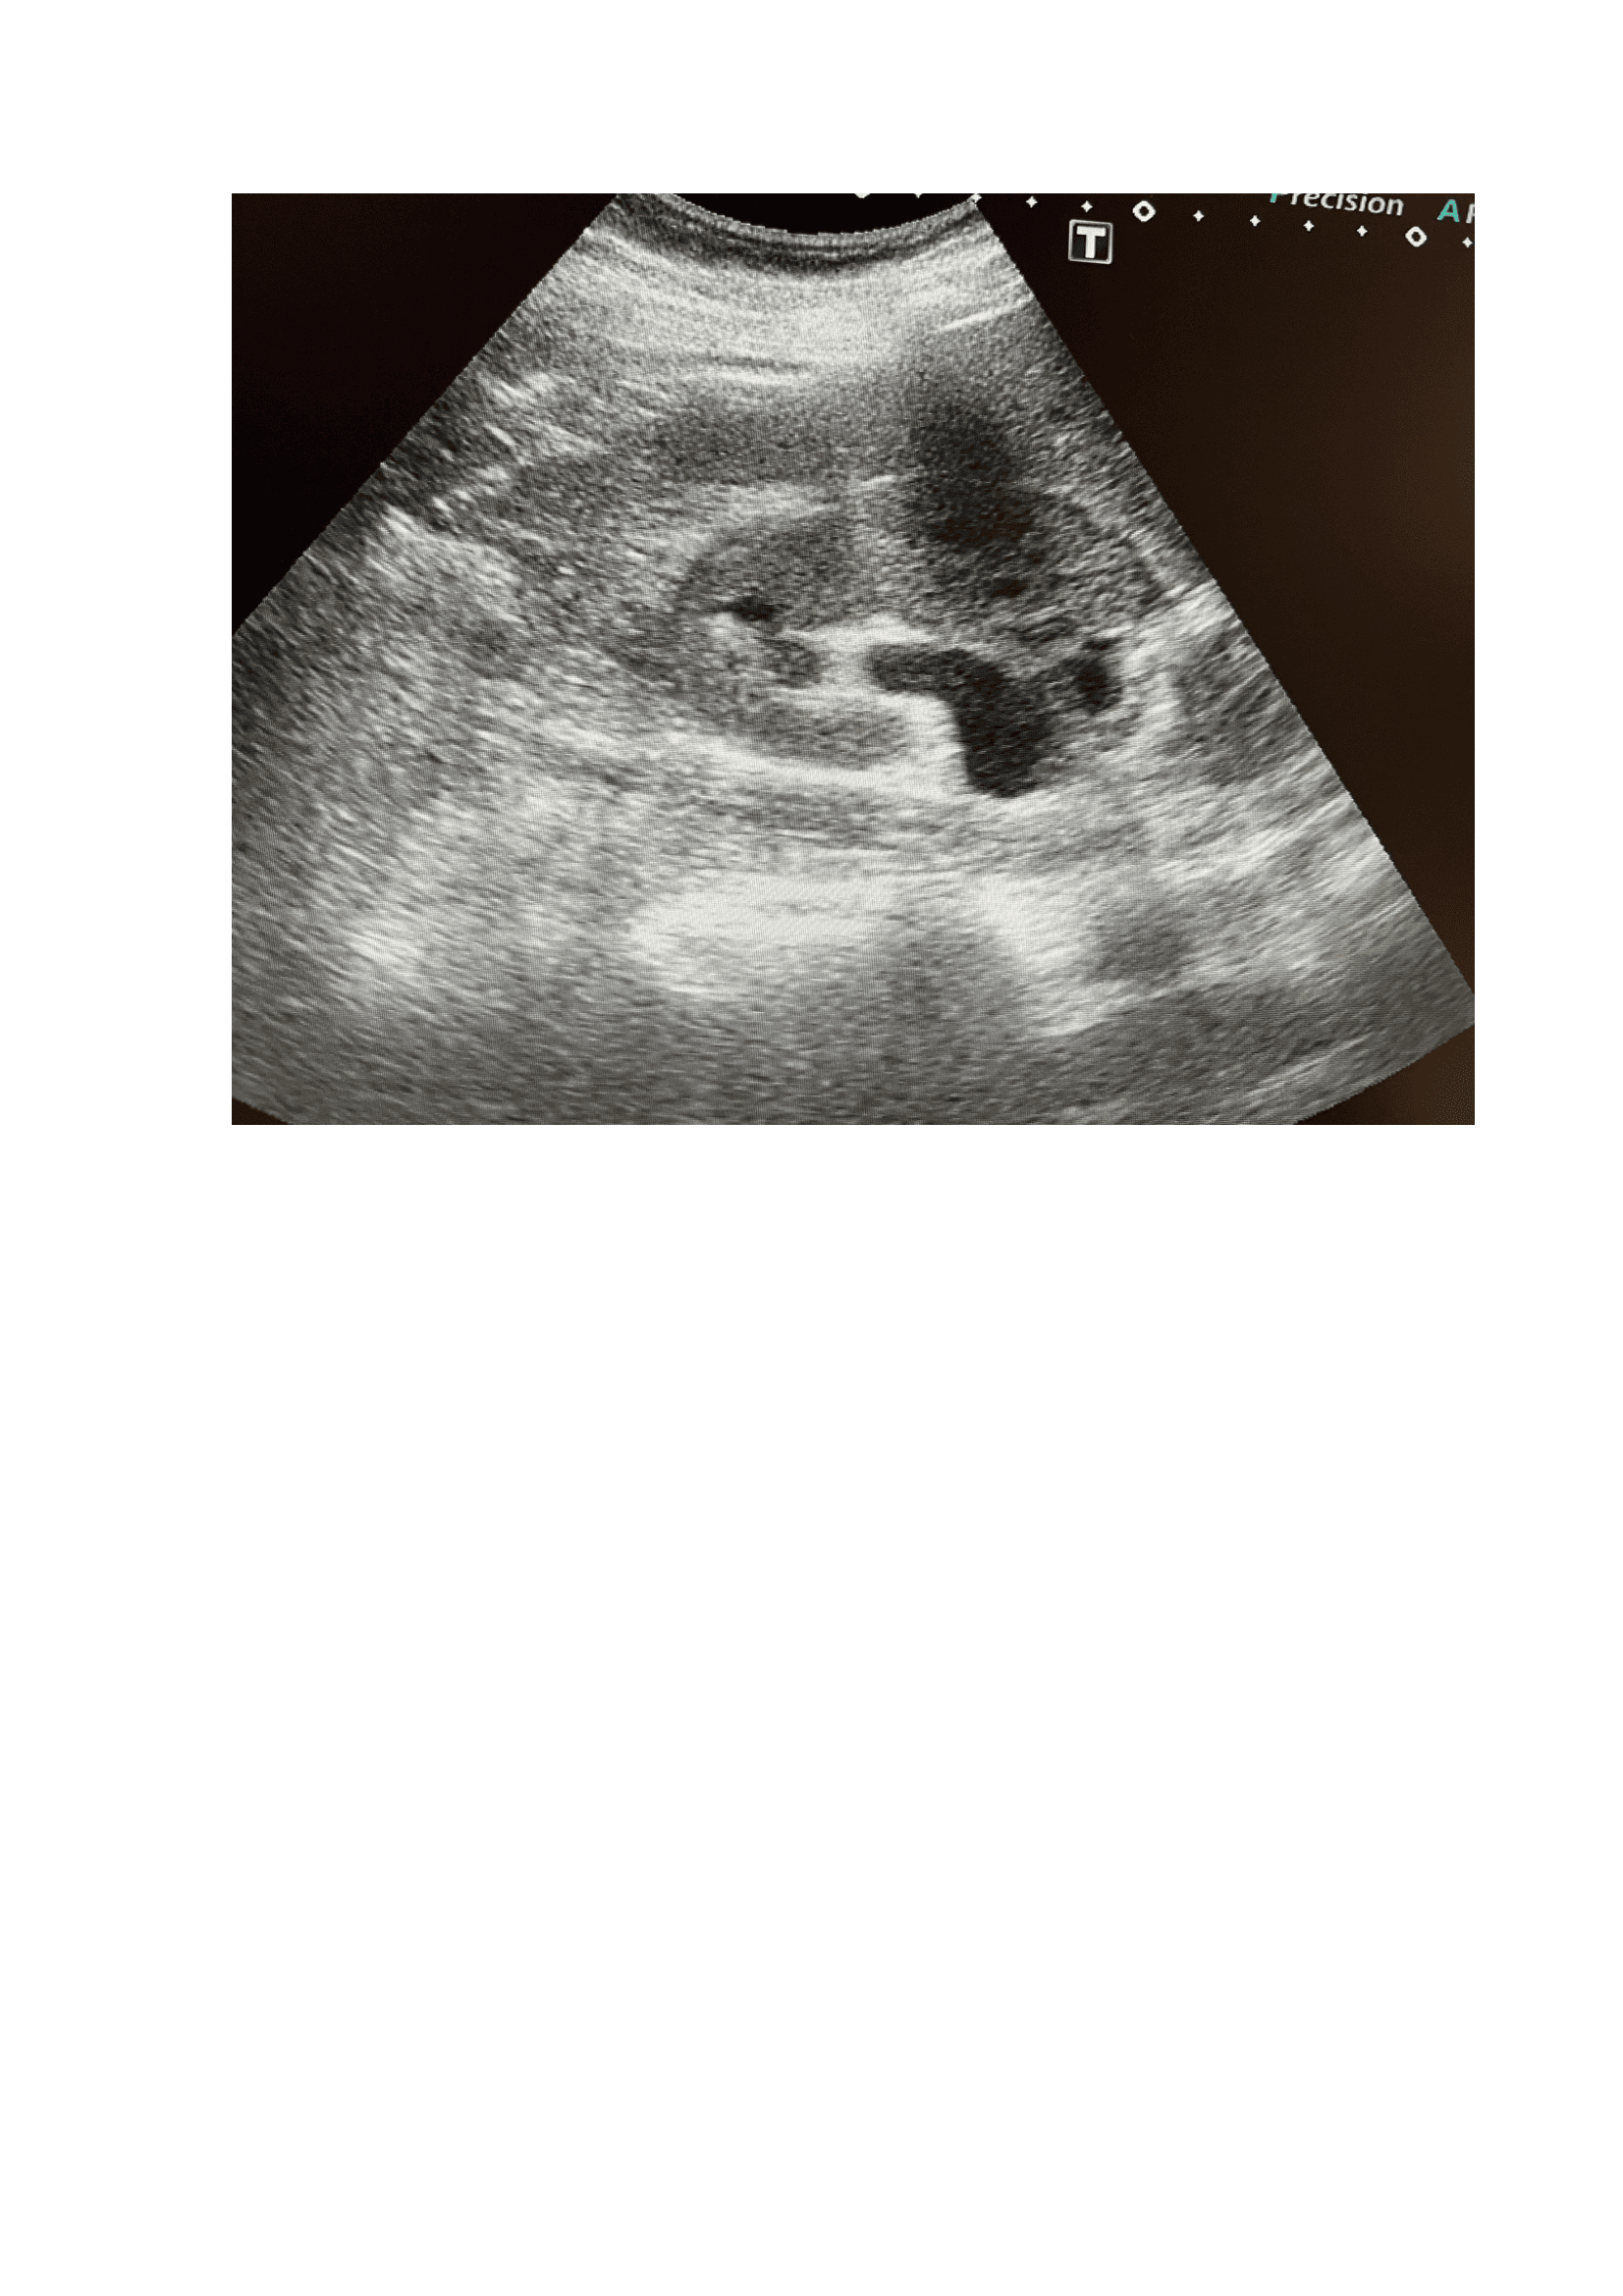

Exploración física, fiebre (39,5 °C) y taquicardia (FC: 120), puño-percusión positiva en la fosa lumbar derecha, sugiriendo una patología renal. Se realiza POCUS) que revela un riñón derecho aumentado de tamaño con una imagen lítica compatible con un cálculo renal de 1,2 cm x 8 mm, junto con dilatación de la pelvis renal (hidronefrosis grado I-II). Una tomografía computarizada (TAC) confirma los hallazgos y muestra un cálculo renal de 4 mm en la zona vesicoureteral distal, no obstruyendo totalmente la vía urinaria.

Urología: evidencia mejoría del cuadro clínico, niega fiebre, dolor. Refiere expulsión de pequeño cálculo tras 5 días de tratamiento. Ecografía, Riñón de tamaño normal, homogéneo, se evidencia imagen litiásica que deja sombra acústica posterior de 1,2 cm x 9 mm aprox. que no compromete vía urinaria, no dilatación de pelvis renal. Se deja tratamiento con tamsulosina durante 3 meses hasta nueva valoración. Control con su médico de familia, solicitar seguimiento de niveles ácido úrico y si alteración pautar tratamiento.